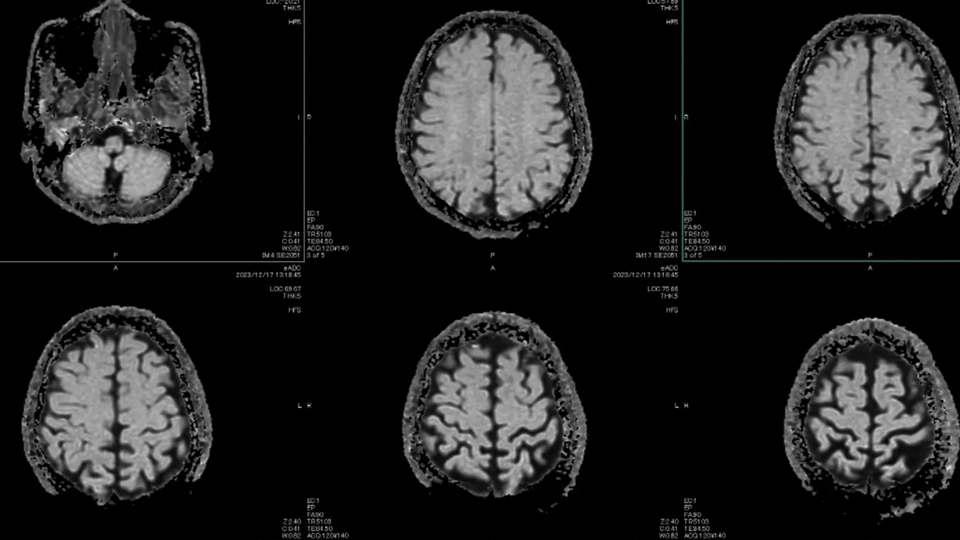

Gần một thập kỷ trước, Geoffrey Hinton, người được xem là "cha đẻ của AI", tuyên bố các bệnh viện nên ngừng đào tạo bác sĩ X quang vì AI sẽ làm tốt hơn trong vòng 5 năm. Điều gì đã xảy ra? Số bác sĩ X quang hiện nay nhiều hơn bao giờ hết. Trong số gần 950 công cụ AI được FDA phê duyệt từ 1995 đến 2024, có 723 thiết bị liên quan đến X quang. Máy móc tiến bộ, nhưng con người vẫn ở đó. Hinton sau đó thừa nhận ông không tính sai về công nghệ, mà tính sai về kinh tế: nhu cầu chăm sóc sức khỏe thực chất là vô hạn, đặc biệt với người cao tuổi, và AI giúp bộc lộ phần nhu cầu chưa từng được đáp ứng, chứ không thay thế nhân lực.